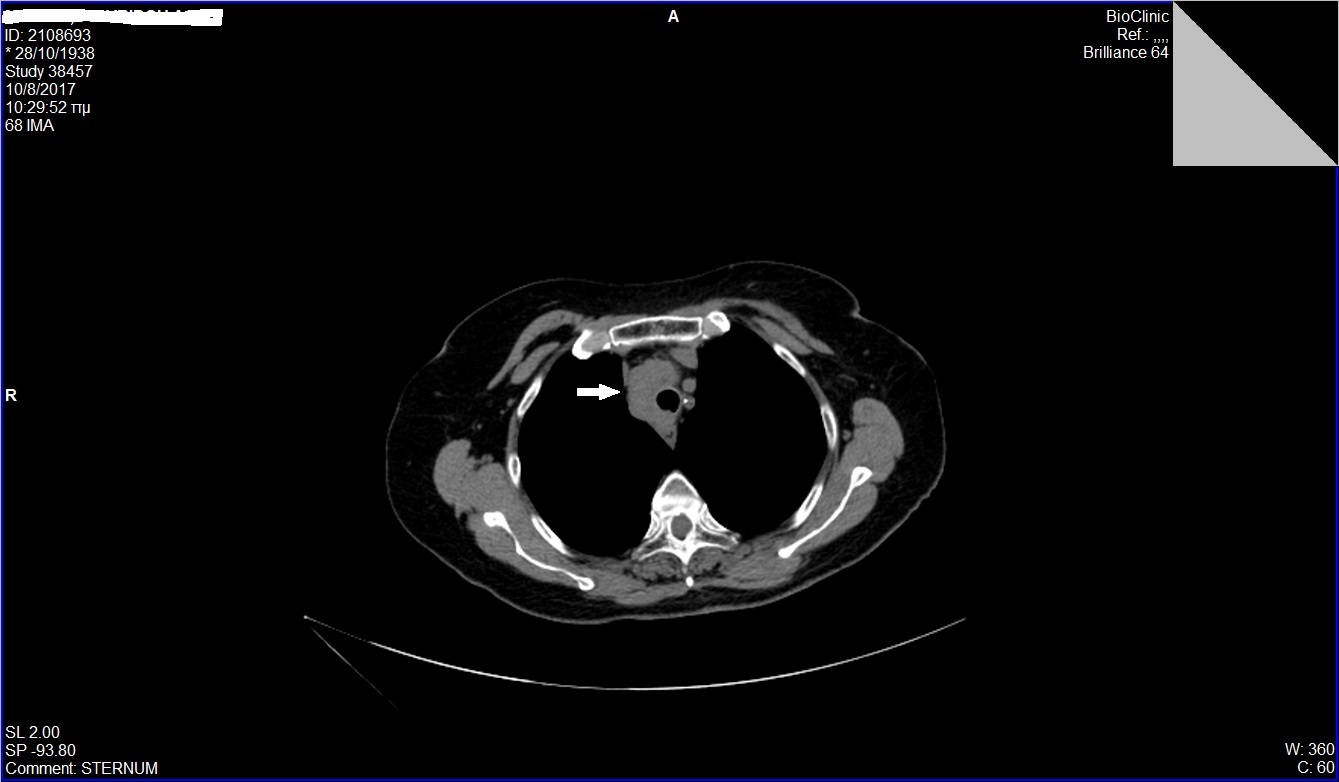

Άνδρας 43 ετών, χωρίς προηγούμενο ατομικό ή οικογενειακό ιστορικό, εμφάνισε επίμονους εμέτους και επιγαστραλγία. Υποβλήθηκε σε αξονική τομογραφία θώρακος, άνω και κάτω κοιλίας από το θεράποντα ιατρό του που έδειξε διάχυτη θωρακική και κοιλιακή λεμφαδενοπάθεια, με διογκωμένους λεμφαδένες στον υποτροπιδικό χώρο, στον αλλήρειο τρίποδα, στον ηπατοδωδεκαδακτυλικό σύνδεσμο και πέριξ του παγκρέατος. Ο ασθενής παραπέμφθηκε για ενδοσκοπικό υπέρηχο και λήψη βιοψιών από τους λεμφαδένες. Έγινε βιοψία με ειδική βελόνα για λήψη ιστοτεμαχίων (Pro-Core 19g) από λεμφαδένες σε 3 διαφορετικές θέσεις (υποτροπιδικά, αλληρείου τρίποδα και ηπατοδωδεκαδακτυλικού συνδέσμου). Η ιστολογική εξέταση και ο ανοσοϊστοχημικός έλεγχος έδειξε αδενοκαρκίνωμα χαμηλής διαφοροποίησης χωρίς θετικότητα στις επιμέρους, ειδικές χρώσεις. Ο ενδοσκοπικός έλεγχος του πεπτικού επιβεβαίωσε την ύπαρξη νεο-εξεργασίας στην ηπατική καμπή του παχέος εντέρου που ιστολογικά ήταν ένα αδενοκαρκίνωμα χαμηλής διαφοροποίησης. Ο ασθενής παραπέμφθηκε για προεγχειρητική χημειοθεραπεία και χειρουργική αντιμετώπιση.

CT: υποτροπιδικός λεμφαδένας

Γυναίκα 79 ετών παρουσίασε απώλεια βάρους 5 κιλών από 3μήνου, χωρίς άλλα συμπτώματα. Από το ατομικό αναμνηστικό της ήταν καπνίστρια ενός πακέτου τσιγάρων επί τουλάχιστον 40 χρόνια. Στην αξονική τομογραφία (CT) θώρακος και άνω-κάτω κοιλίας διαπιστώθηκε μια παρατραχειακή μάζα μεσοθωρακίου, διαμέτρου 3εκ. Η μάζα εκτεινόταν μπροστά από την τραχεία, κυκλοτερώς προς τα δεξιά της, μέχρι όπισθεν της και παραοισοφαγικά. Η ασθενής υποβλήθηκε αρχικά σε βρογχοσκόπηση που ήταν φυσιολογική χωρίς να τεθεί η διάγνωση και στη συνέχεια παραπέμφθηκε για βιοψία της μάζας με ενδοσκοπικό υπέρηχο (EUS). Στον ενδοσκοπικό υπέρηχο, η μάζα ήταν υποηχοϊκή, ανομοιογενής, με αγγειοβρίθεια . Έγινε βιοψία με λεπτή βελόνη 22g (FNA X 3) από διαφορετικές θέσεις της μάζας. Η κυτταρολογική εξέταση με cell block έδειξε μορφολογικά και ανοσοφαινοτυπικά ευρήματα συμβατά με μικροκυτταρικό καρκίνωμα πνεύμονα (θετική ανοσοϊστοχημεία σε TTF-1, CD56 και γενική κερατίνη). Η ασθενής παραπέμφθηκε σε ογκολόγο για έναρξη χημειοθεραπείας.

CT θώρακος: παρατραχειακή μάζα (βέλος)